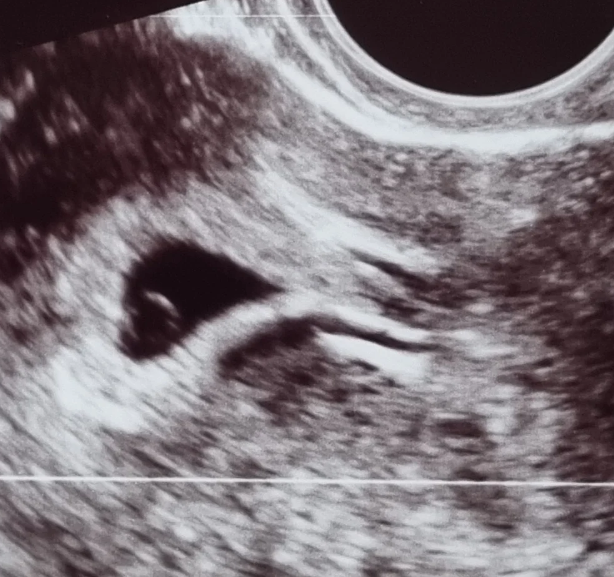

Een gemis van vóór de geboorte

Een gemis dat je niet altijd met je hoofd kunt plaatsen, maar dat je lichaam al lang kent. Soms voel je iets in jezelf wat je moeilijk onder woorden kunt brengen. Een leegte, een zoeken naar iets of iemand. Een diepe eenzaamheid, zelfs als je omringd bent door liefdevolle mensen. In mijn praktijk zie ik geregeld dat dit gevoelens zijn die zijn verbonden met een vroege ervaring: het verlies van een twee- of meerlinghelft in de baarmoeder.

Dit noemen we het alleengeboren tweeling- (of meerling)trauma. Het is geen diagnose, maar een innerlijke realiteit die voor veel mensen onbewust meespeelt.

Toen ik zwanger was, kregen we een bloeding. De verloskundige zei: “Jullie zullen het nooit weten, misschien was er een tweede vrucht.” We legden ons erbij neer — niet wetend dat dit stukje verleden later opnieuw voelbaar zou worden.